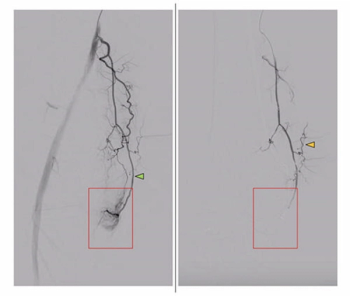

In a cohort of over 160 patients with knee osteoarthritis (OA), including grade 4 in nearly half of the cases, genicular artery embolization led to an 87 percent improvement in the quality of life index, according to research presented at the recent RSNA conference.